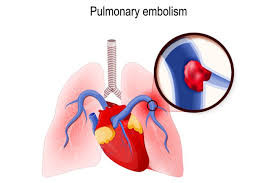

Embolisme paru (pulmonary embolism, PE) adalah kondisi tersumbatnya arteri pada paru-paru yang disebabkan oleh bekuan darah yang terlepas. Bekuan darah ini berasal dari bagian tubuh yang lain, seperti lengan atau tungkai, yang terlepas dan mengikuti aliran udara hingga paru. Sumbatan pembuluh darah yang disebabkan oleh bekuan darah dapat mengancam jiwa.

Embolisme paru disebabkan oleh bekuan darah yang menyumbat aliran darah pada paru. Bekuan darah ini paling sering berasal dari tungkai, yaitu akibat penyakit yang disebut trombosis vena dalam (deep vein thrombosis, DVT). Pada sebagian besar kasus, sumbatan tidak hanya terjadi pada satu pembuluh darah, sehingga beratnya gejala akan bervariasi tergantung pada seberapa banyak pembuluh darah yang tersumbat. Jika pembuluh darah tertentu tersumbat, jaringan paru yang diperdarahi oleh pembuluh darah tersebut akan mati, menyebabkan infark paru. Infark paru menyebabkan semakin terganggunya proses pertukaran oksigen di paru yang mempengaruhi tingkat oksigen secara keseluruhan.

Embolisme paru dapat mengancam nyawa. Sekitar satu dari tiga orang yang terlambat didiagnosis dan ditangani meninggal dunia. Jika kondisi ini dapat dideteksi dengan lebih cepat, kemungkinan sembuh lebih tinggi.

Embolisme paru juga dapat menyebabkan hipertensi pulmonal, yaitu kondisi dimana tekanan darah pada paru dan jantung kanan terlalu tinggi. Jika terjadi sumbatan pada arteri paru, jantung perlu bekerja lebih keras untuk mendorong darah melalui pembuluh darah, sehingga meningkatkan tekanan darah dan melemahkan otot jantung.

Pada beberapa kasus, emboli dapat menyumbat sedikit demi sedikit dalam waktu lama, sehingga terjadi hipertensi pulmonal kronis.